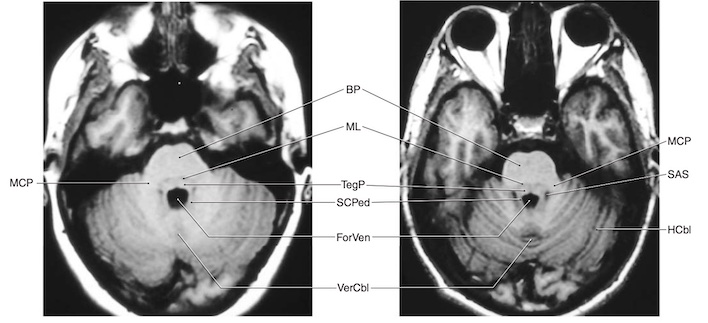

Các cuống tiểu não:

Tiểu não nối với thân não và qua đó với các phần khác của hệ thần kinh bằng 3 đôi cuống tiểu não:

- Cuống tiểu não trên nối với não giữa (chủ yếu là đầu ra đến vỏ não vận động qua trung gian các nhân đồi thị)

- Cuống tiểu não giữa nối với cầu não (nhận đầu vào từ các nhân ở cầu não, trung chuyển từ vỏ não đến tiểu não).

- Cuống tiểu não dưới nối với hành não (nhận đầu vào từ các nhân tiền đình, tuỷ sống và mái và xuất đầu ra đến các nhân tiền đình).

Như vậy, các đầu vào đến tiểu não chủ yếu qua các cuống tiểu não dưới và giữa, trong khi đầu ra chủ yếu được chuyển qua cuống tiểu não trên. Không như vỏ đại não, tiểu não nhận thông tin và gởi thông tin đến nửa cùng bên của cơ thể, và tổn thương tiểu não do đó dẫn đến các khiếm khuyết cùng bên.